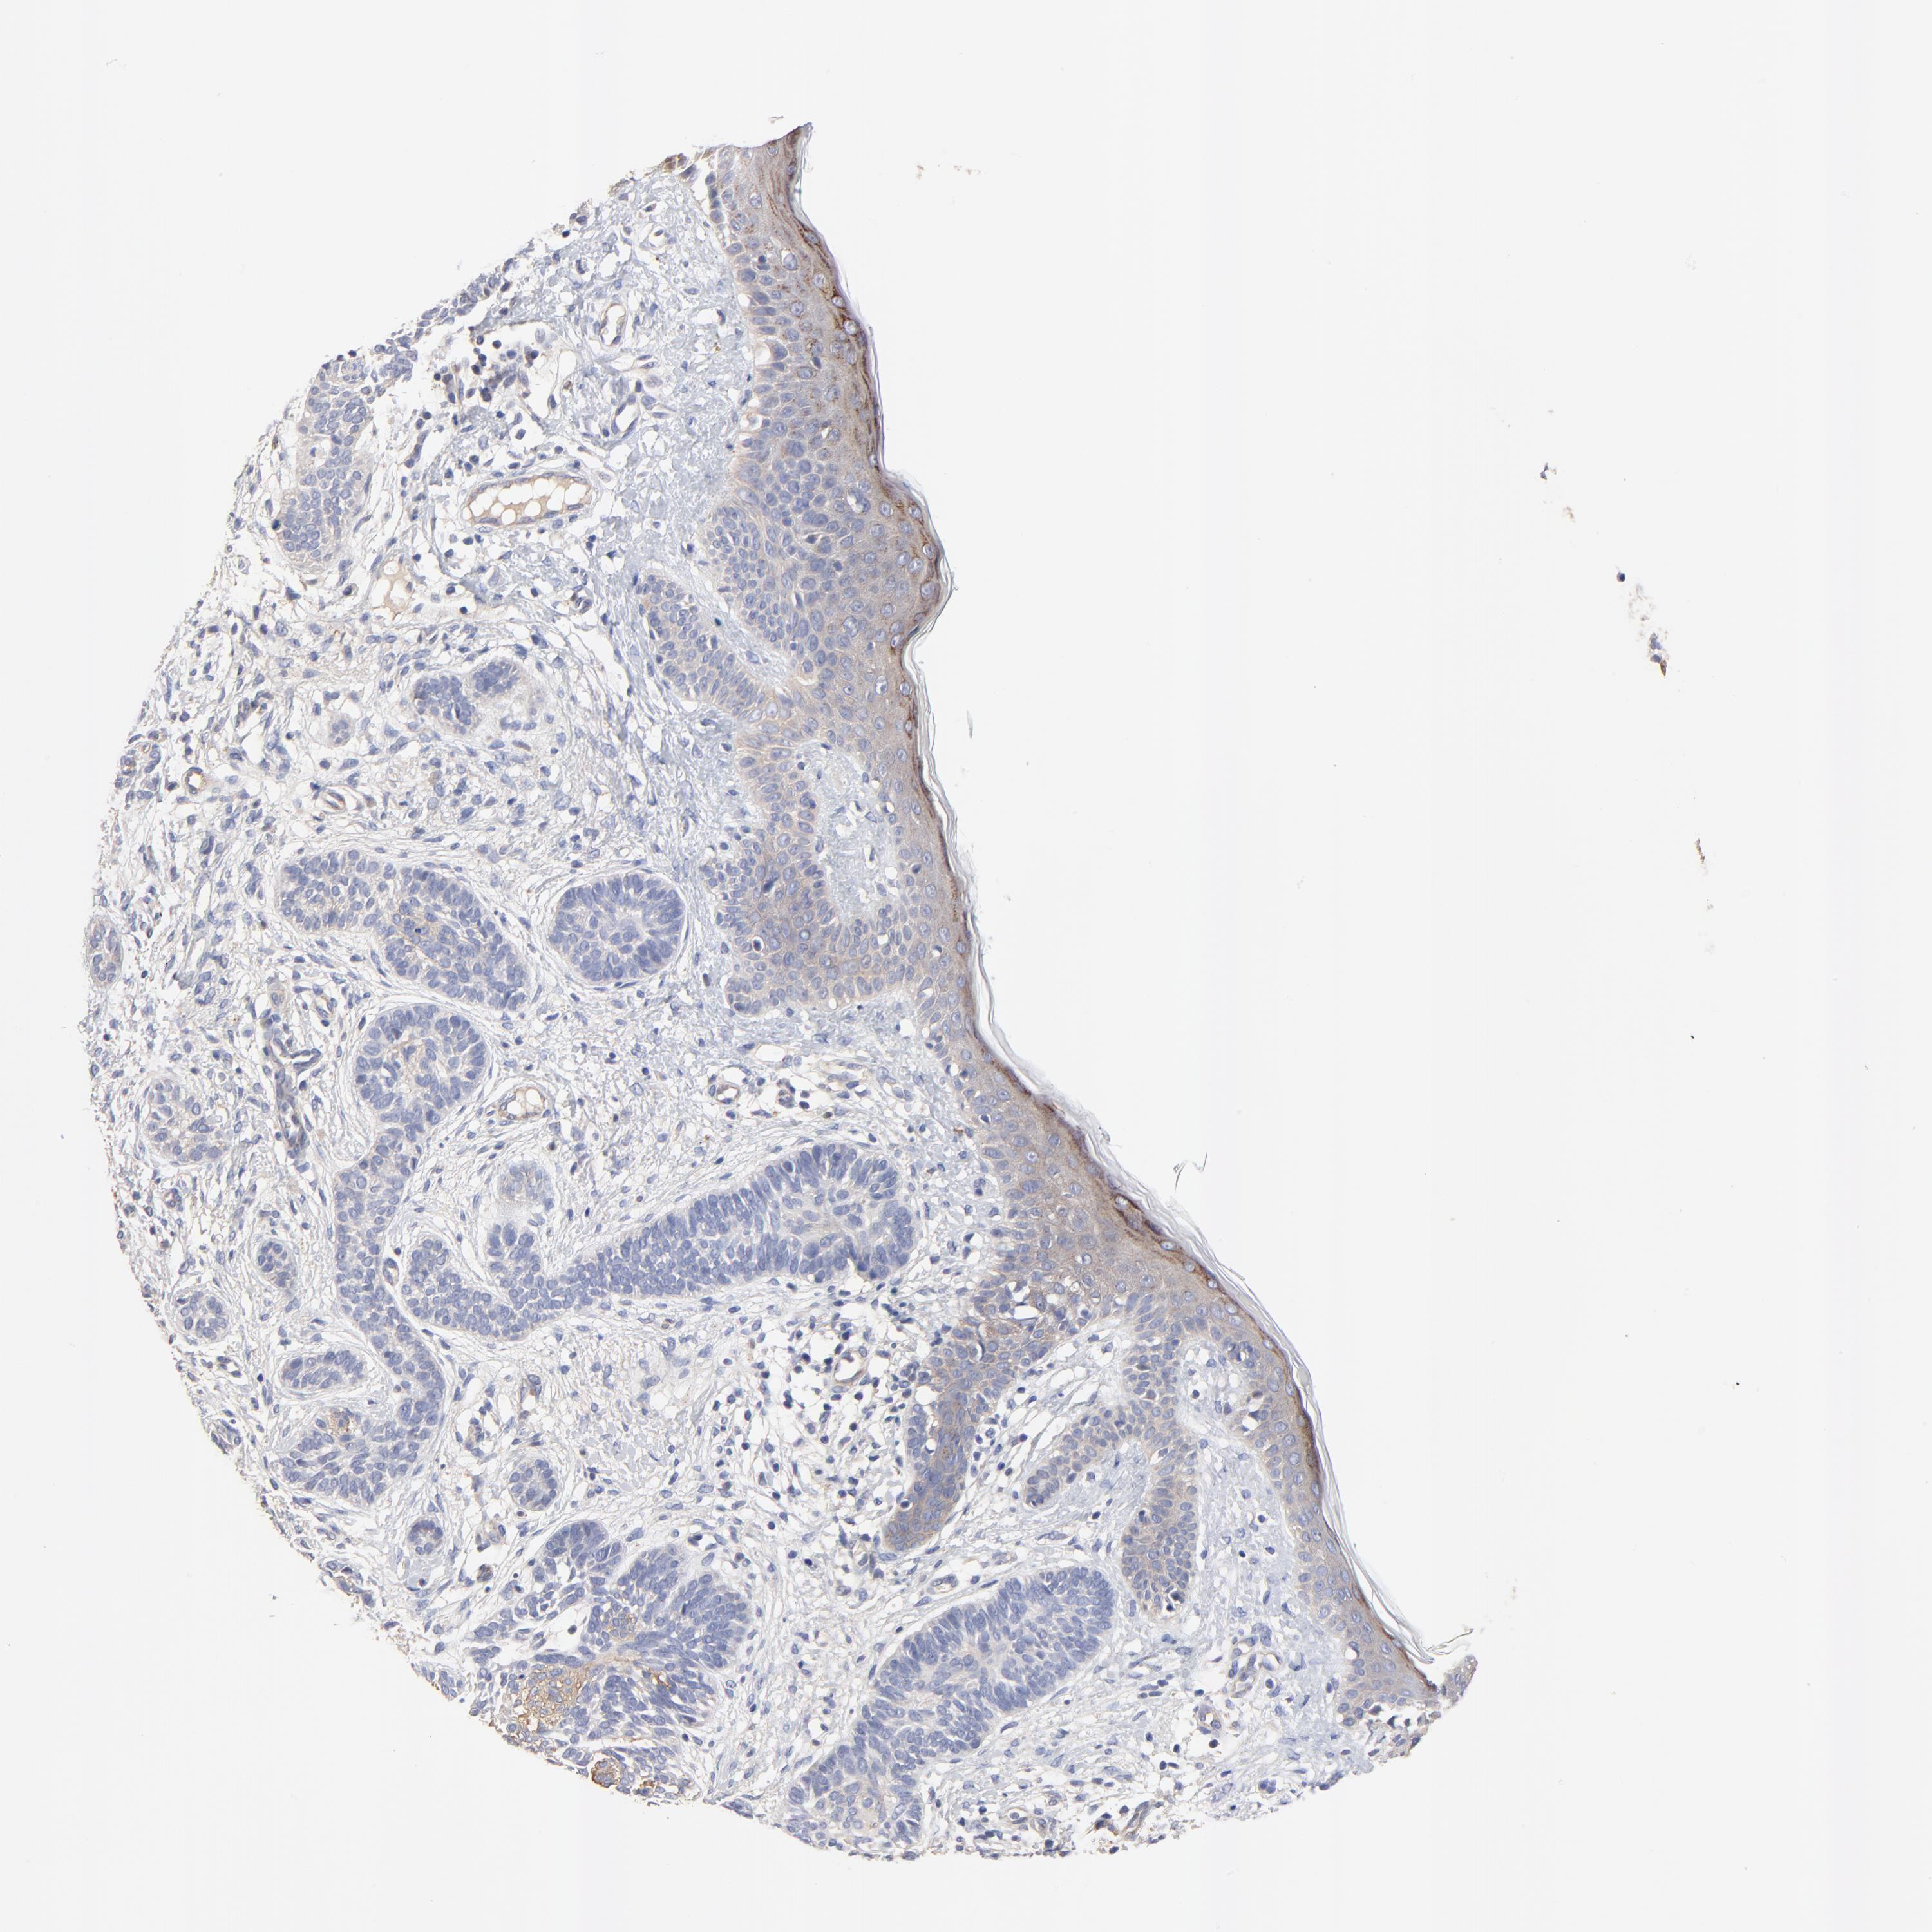

SKIN CANCER - Protein expressioni

A mouse-over function shows sample information and annotation data. Click on an image to view it in a full screen mode. Samples can be filtered based on level of antibody staining by selecting one or several of the following categories: high, medium, low and not detected. The assay and annotation is described here.

Each image is clickable and will lead to virtual microscopy that enables deeper exploration of all samples and also displays staining intensity scores, fraction scores and subcellular localization as well as patient and tissue information for each sample.

Antibody HPA003240

Squamous cell carcinoma, NOS